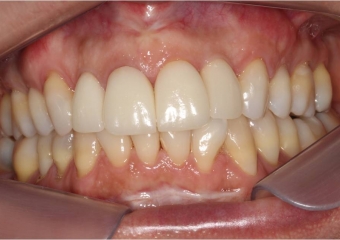

Sorriso inicial - Clínica Cliniface

Sorriso inicial